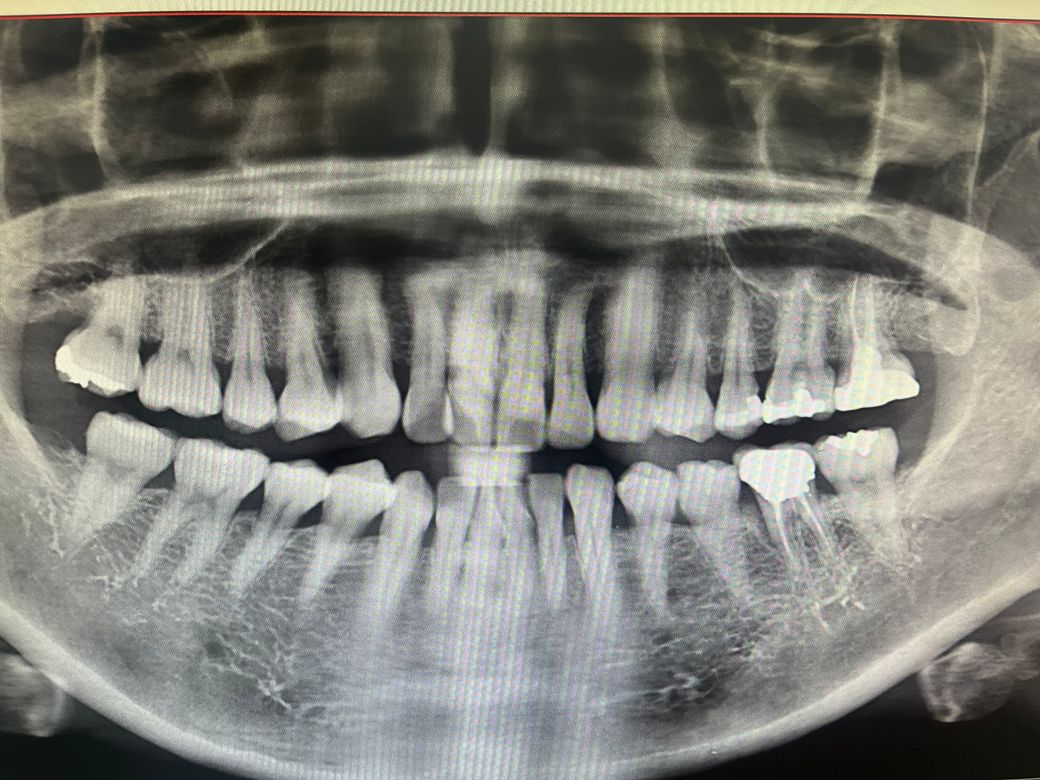

크라운하기전 사진

상악동염은 파노라마 사진상에서는 관찰되지 않는 듯 합니다. 신경치료를 했던 곳에서 다시 평가 받아보셔야겠습니다.

사진상으로는 상악동에 염증이 있거나 그래 보이진 않습니다. 보철문제인거 같으니 보철을 봐주는 대학병원 보철과를 한번 가보세요.

파노라마 사진상 상악동이 지저분해 보이거나 염증양상은 아닙니다.